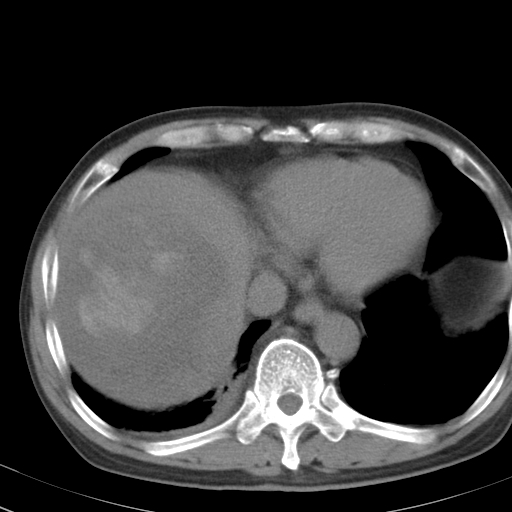

以下是引用卜一在2008-6-23 15:38:00的发言:[br]本例延时期的图象未扫完,单纯平扫 动脉期及门脉期特征分析:平扫低密度较大肿块,内见不规则出血灶,界限清楚。动脉期边缘结节样强化,门脉期病灶边缘进一步强化并范围明显缩小。因此考虑:血管瘤伴出血!

以下是引用深泽交通医院在2008-6-23 16:40:00的发言:[br]考虑肝癌伴出血.诊断依据:平扫瘤壁结节密度低于肝实质,动脉期壁结节明显强化,门脉期略低于肝实质密度[br]病灶有明显的假包膜,